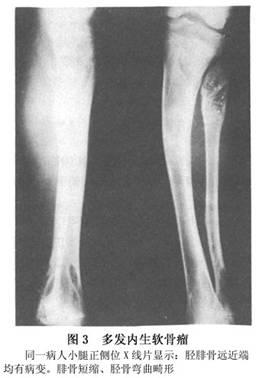

多发性遗传畸形性软骨发育异常

图片尺寸262x378